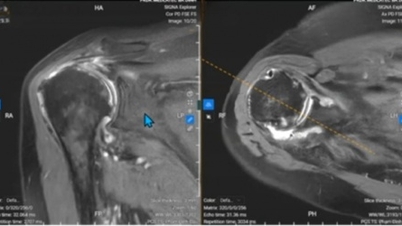

Плечевой сустав состоит из плечевой кости, лопатки и ключицы. Они соединены мягкими тканями, такими как связки, сухожилия, мышцы и суставные капсулы. Когда лопатка не движется к позвоночнику из-за напряжения мышц, это может привести к её смещению и вызвать импинджмент-синдром, что приводит к ограничению подвижности.